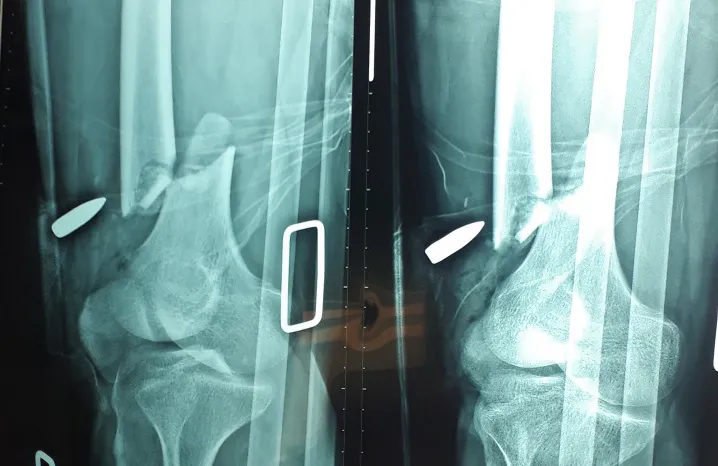

Kết quả chụp X-quang cho thấy anh T. bị gãy xương đùi phải. Ảnh: BVCC

Trong quá trình phẫu thuật, các BS ghi nhận anh T. bị gãy nát 1/3 xương đùi phải. Ngoài ra, các BS còn ghi nhận anh T. bị dập nát, đứt gân cơ từ đầu đùi phải.

Các BS đã cắt lọc sạch mô dập nát hoại tử và rửa vết thương cho bệnh nhân, đồng thời các BS dẫn lưu kín vết thương, khâu gân cơ từ đầu đùi và cầm máu vết thương. Sau đó, các BS khâu phục hồi vết thương từng lớp và xuyên đinh cố định tạm ổ gãy.